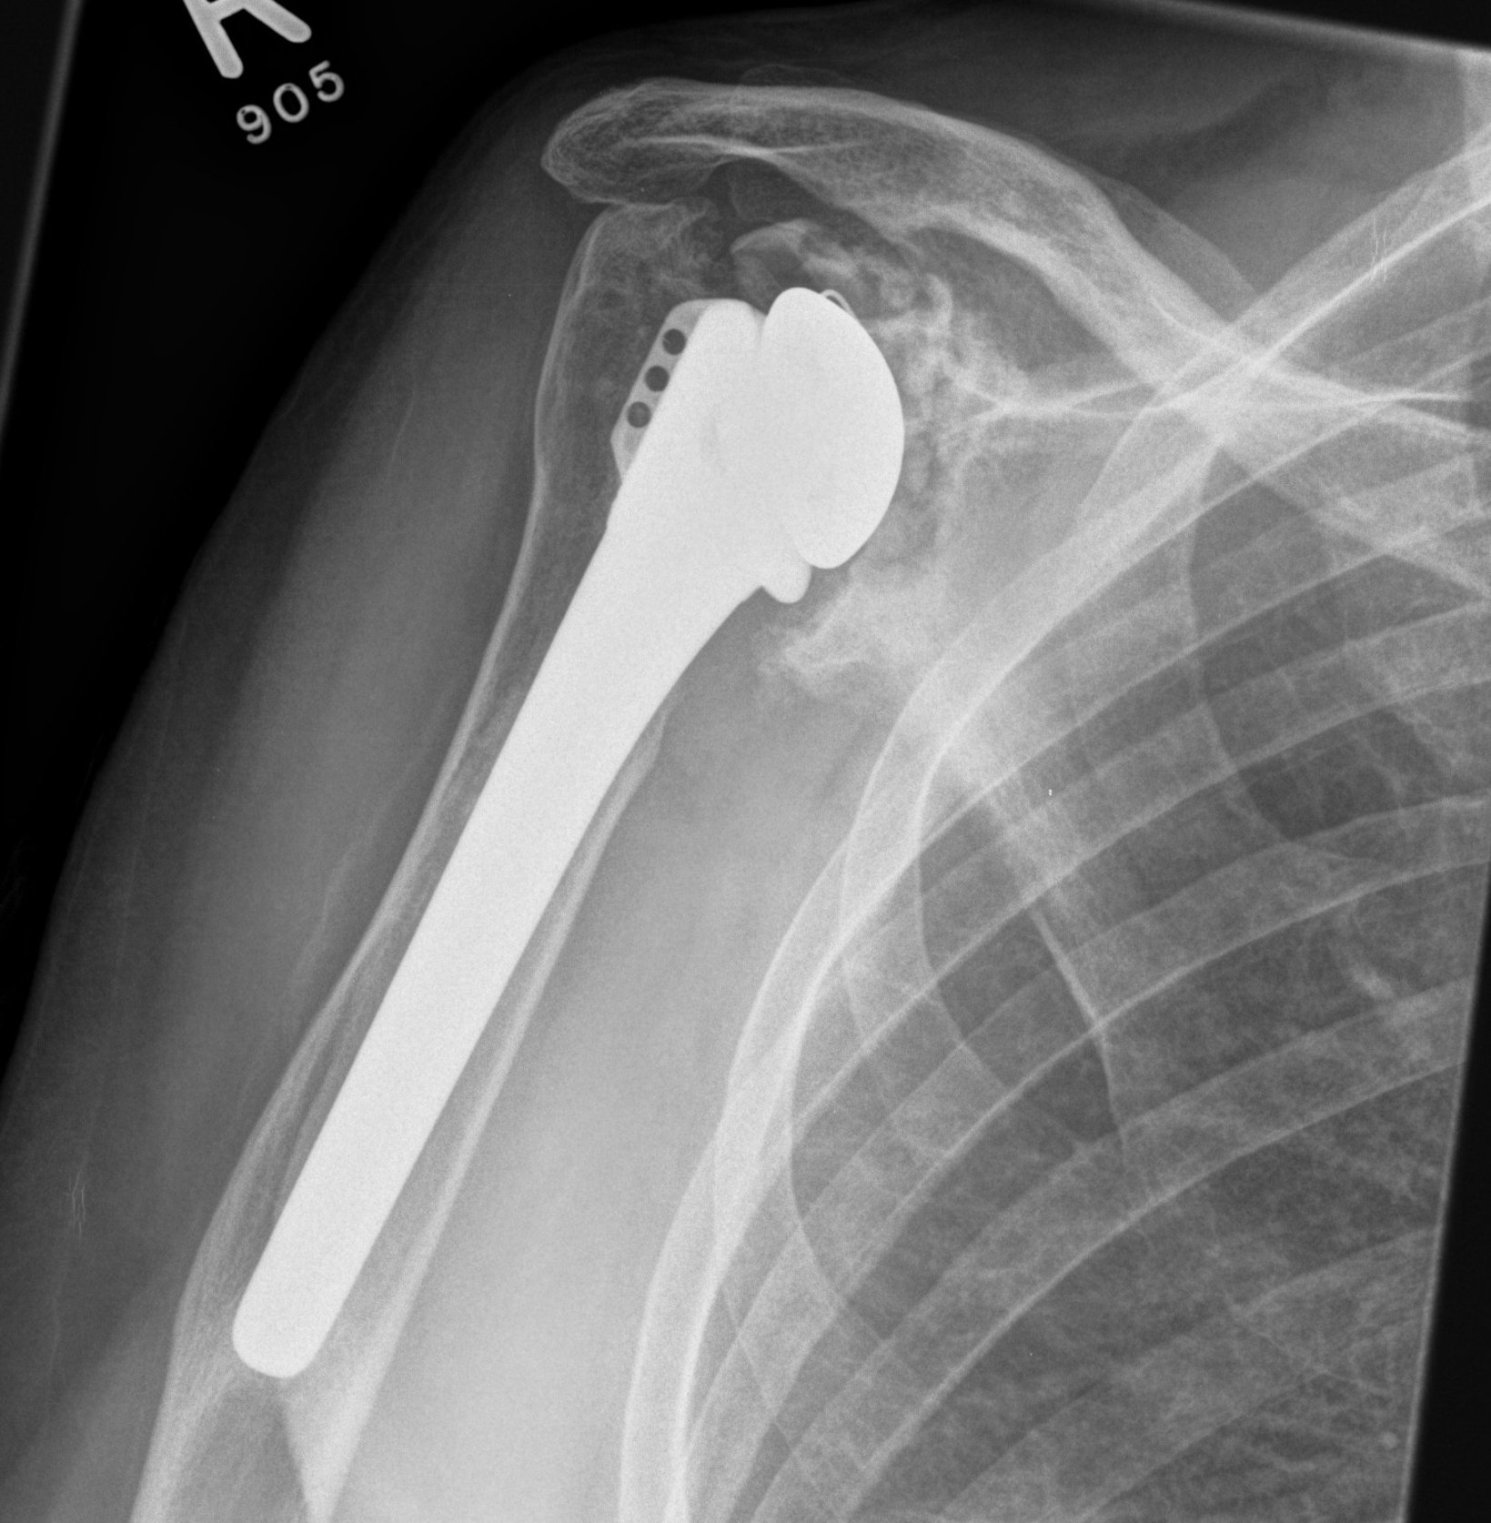

Revision Humeral Component

Technique

- often need long stem

- often use cement in revision circumstance